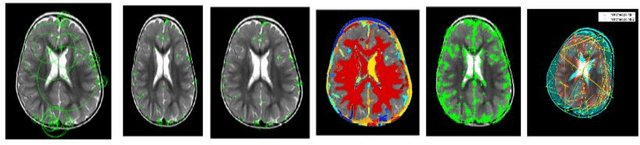

Abstract:Epileptic Seizure is an abnormal neuronal exertion in the brain, affecting nearly 70 million of the world's population (Ngugi et al., 2010). So many open-source neuroimaging tools are used for metabolism checkups and analysis purposes. The scope of open-source tools like MATLAB, Slicer 3D, Brain Suite21a, SPM, and MedCalc are explained in this paper. MATLAB was used by 60% of the researchers for their image processing and 10% of them use their proprietary software. More than 30% of the researchers use other open-source software tools with their processing techniques for the study of magnetic resonance seizure images

Abstract:Glioblastoma brain tumors are highly malignant and often require early detection and accurate segmentation for effective treatment. We are proposing two deep learning models in this paper, namely UNet and Deeplabv3, for the detection and segmentation of glioblastoma brain tumors using preprocessed brain MRI images. The performance evaluation is done for these models in terms of accuracy and computational efficiency. Our experimental results demonstrate that both UNet and Deeplabv3 models achieve accurate detection and segmentation of glioblastoma brain tumors. However, Deeplabv3 outperforms UNet in terms of accuracy, albeit at the cost of requiring more computational resources. Our proposed models offer a promising approach for the early detection and segmentation of glioblastoma brain tumors, which can aid in effective treatment strategies. Further research can focus on optimizing the computational efficiency of the Deeplabv3 model while maintaining its high accuracy for real-world clinical applications. Overall, our approach works and contributes to the field of medical image analysis and deep learning-based approaches for brain tumor detection and segmentation. Our suggested models can have a major influence on the prognosis and treatment of people with glioblastoma, a fatal form of brain cancer. It is necessary to conduct more research to examine the practical use of these models in real-life healthcare settings.